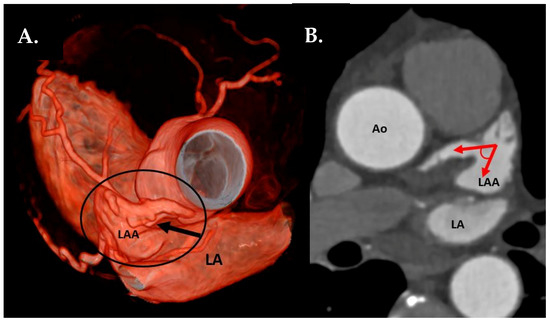

- LAA tip angulation was quantified using multiplanar reformation (MPR) and stratified as follows: ≤90° tip (Figure 2), 91–110°, >110°.